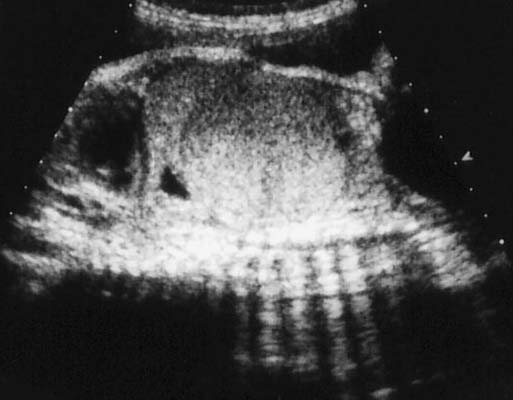

Tumeur de Wilms